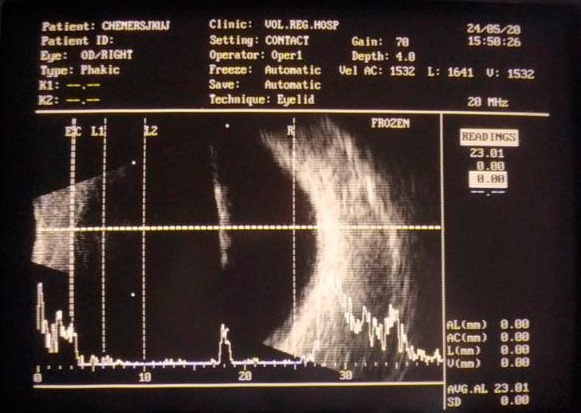

За даними УЗД лікарем Ігорем Стадницьким було з ‘ясовано, що стороннє тіло є досить довгим та проходить в задню камеру ока через весь кришталик.